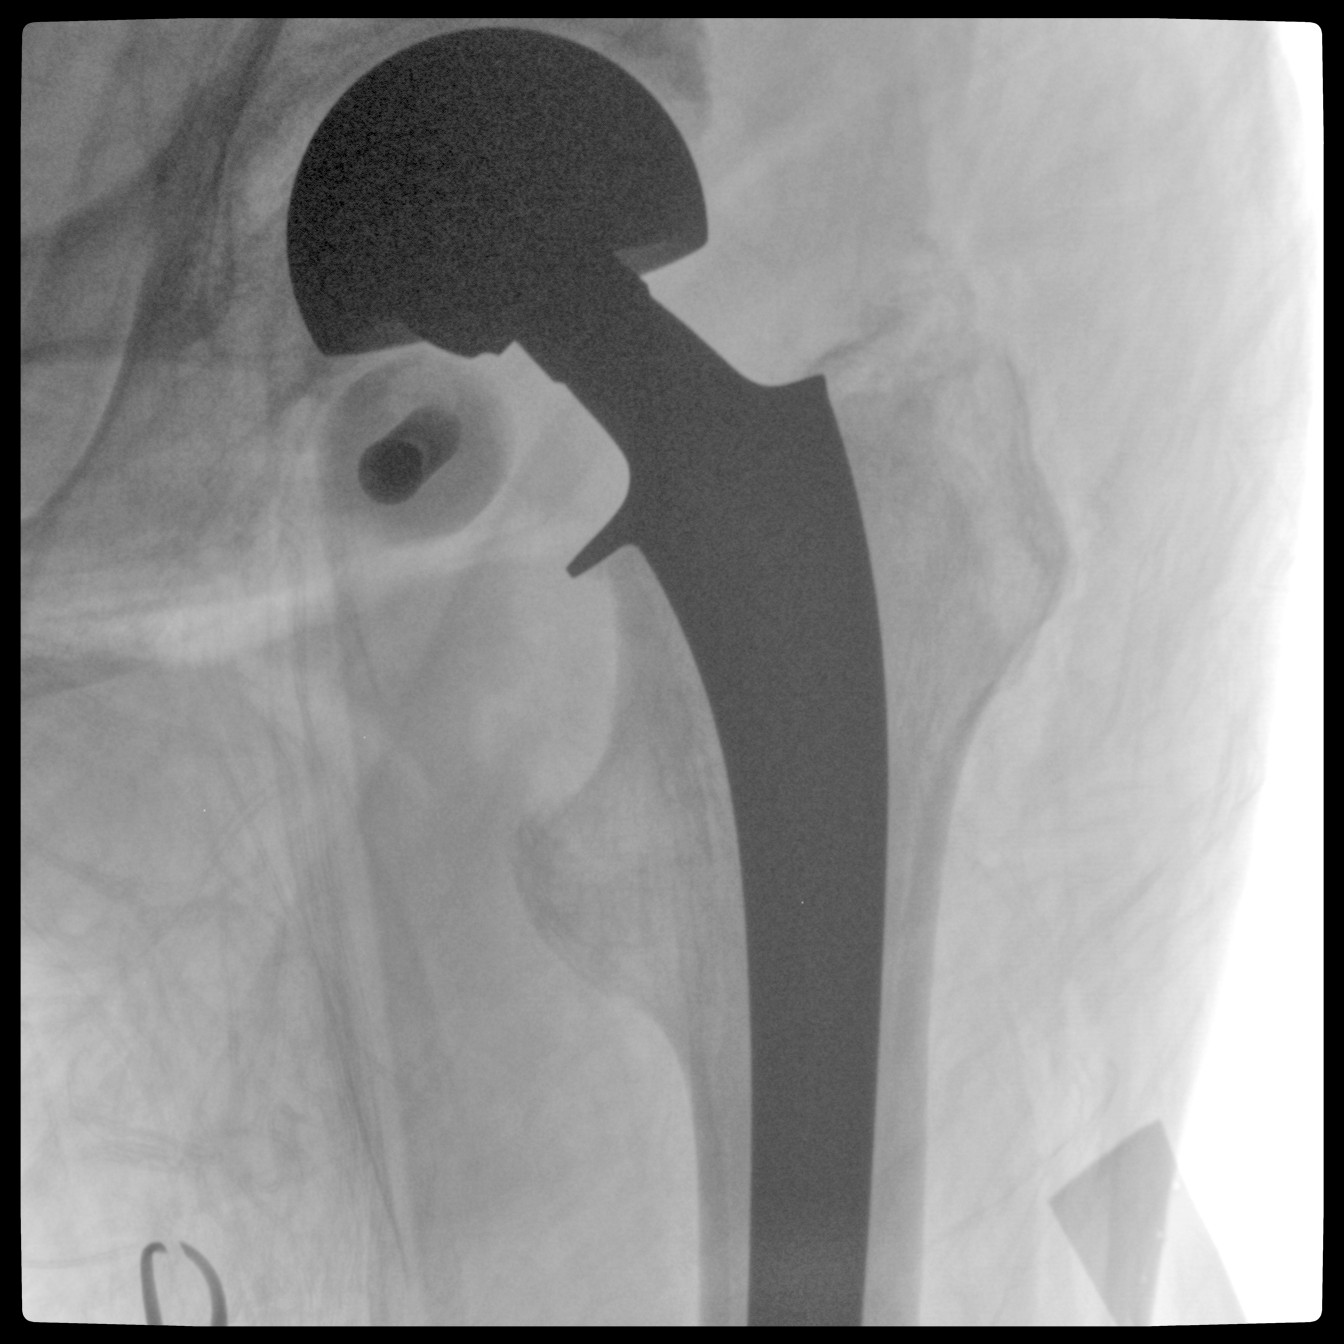

PLX118F-Plus配備了兩種平板尺寸,大尺寸動(dòng)態(tài)平板探測(cè)器成像面積較傳統(tǒng)平板探測(cè)器提升了25%以上,在視野需求大的手術(shù)中,便于醫(yī)生更好定位病灶點(diǎn),規(guī)劃手術(shù)方案,減少因視野范圍不足而多次透視、點(diǎn)片造成的不便。